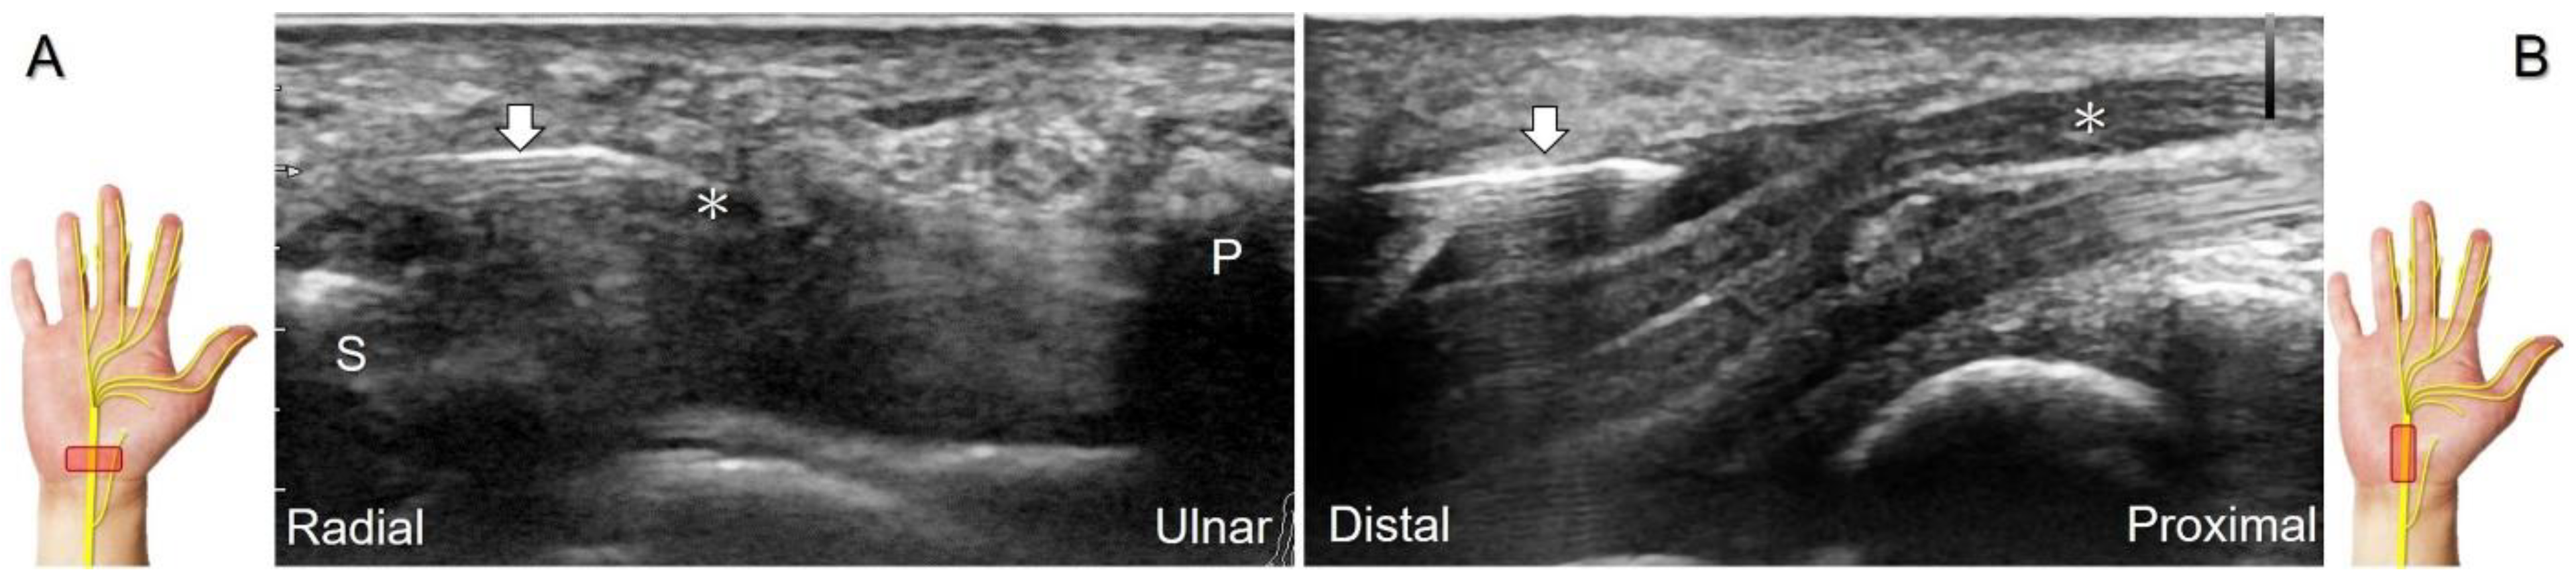

Regarding US-guided injections for carpal tunnel syndrome, a network meta-analysis, including ten studies with 497 patients, reported that 5% dextrose (D5W) injection was likely to be the best treatment for symptom relief, followed by platelet-rich plasma injection [30]. During hydrodissection of the median nerve, the needle can be introduced using either the in-plane approach targeting the short-axis (Figure 6A, Video S1) or long-axis (Figure 6B, Video S2) views of the nerve. If symptoms persist despite non-operative management, consideration should be given to minimal invasive carpal tunnel release, with confirmation of complete release using dynamic US [31].

Figure 6. Ultrasound-guided hydrodissection of the median nerve under short-axis (A) or long-axis (B) imaging. Asterisk: median nerve; arrows: needle. S: scaphoid; P: pisiform.